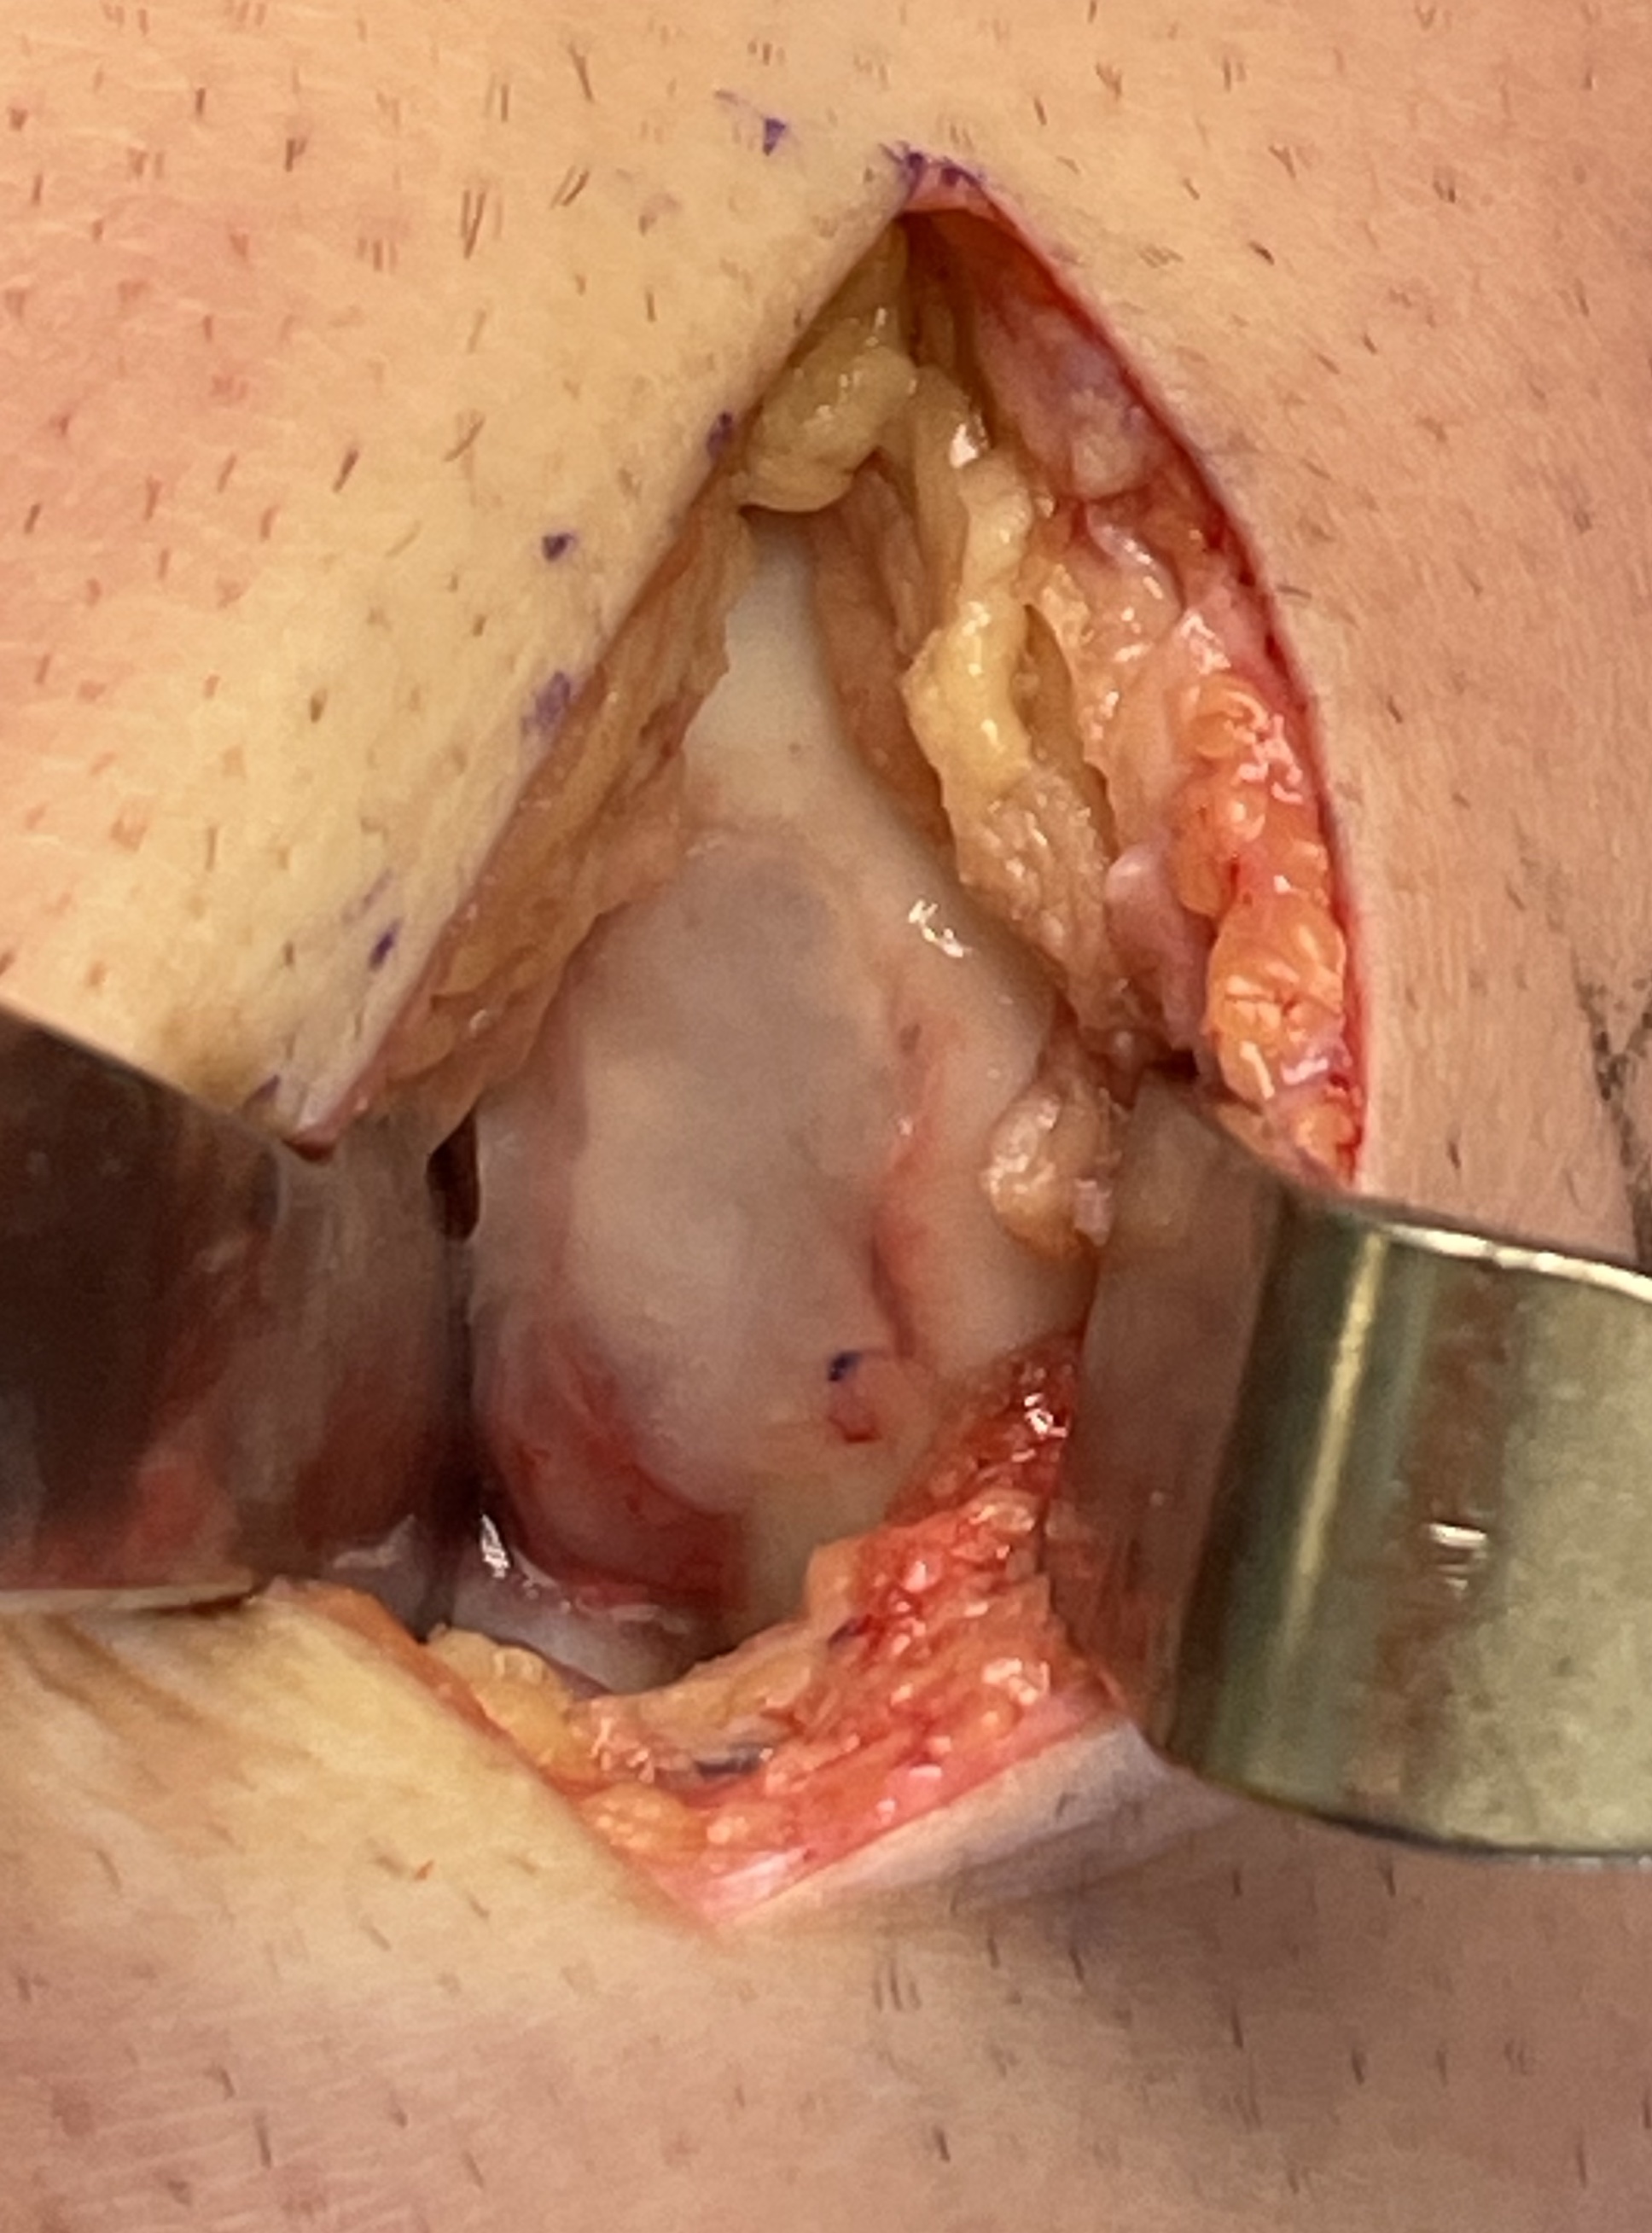

Medial or lateral parapatellar approach

- create sharp stable margins

- curette base / microdrill

- control bleeding with adrenalin soaked gauze to avoid graft displacement

- size defect with foil - graft cannot be prominent or will displace with ROM

- porcine collagen

- bilayer collagen I/III membrane

- secure with fibrin glue / Tisseel

- ensure graft stability with knee range of motion